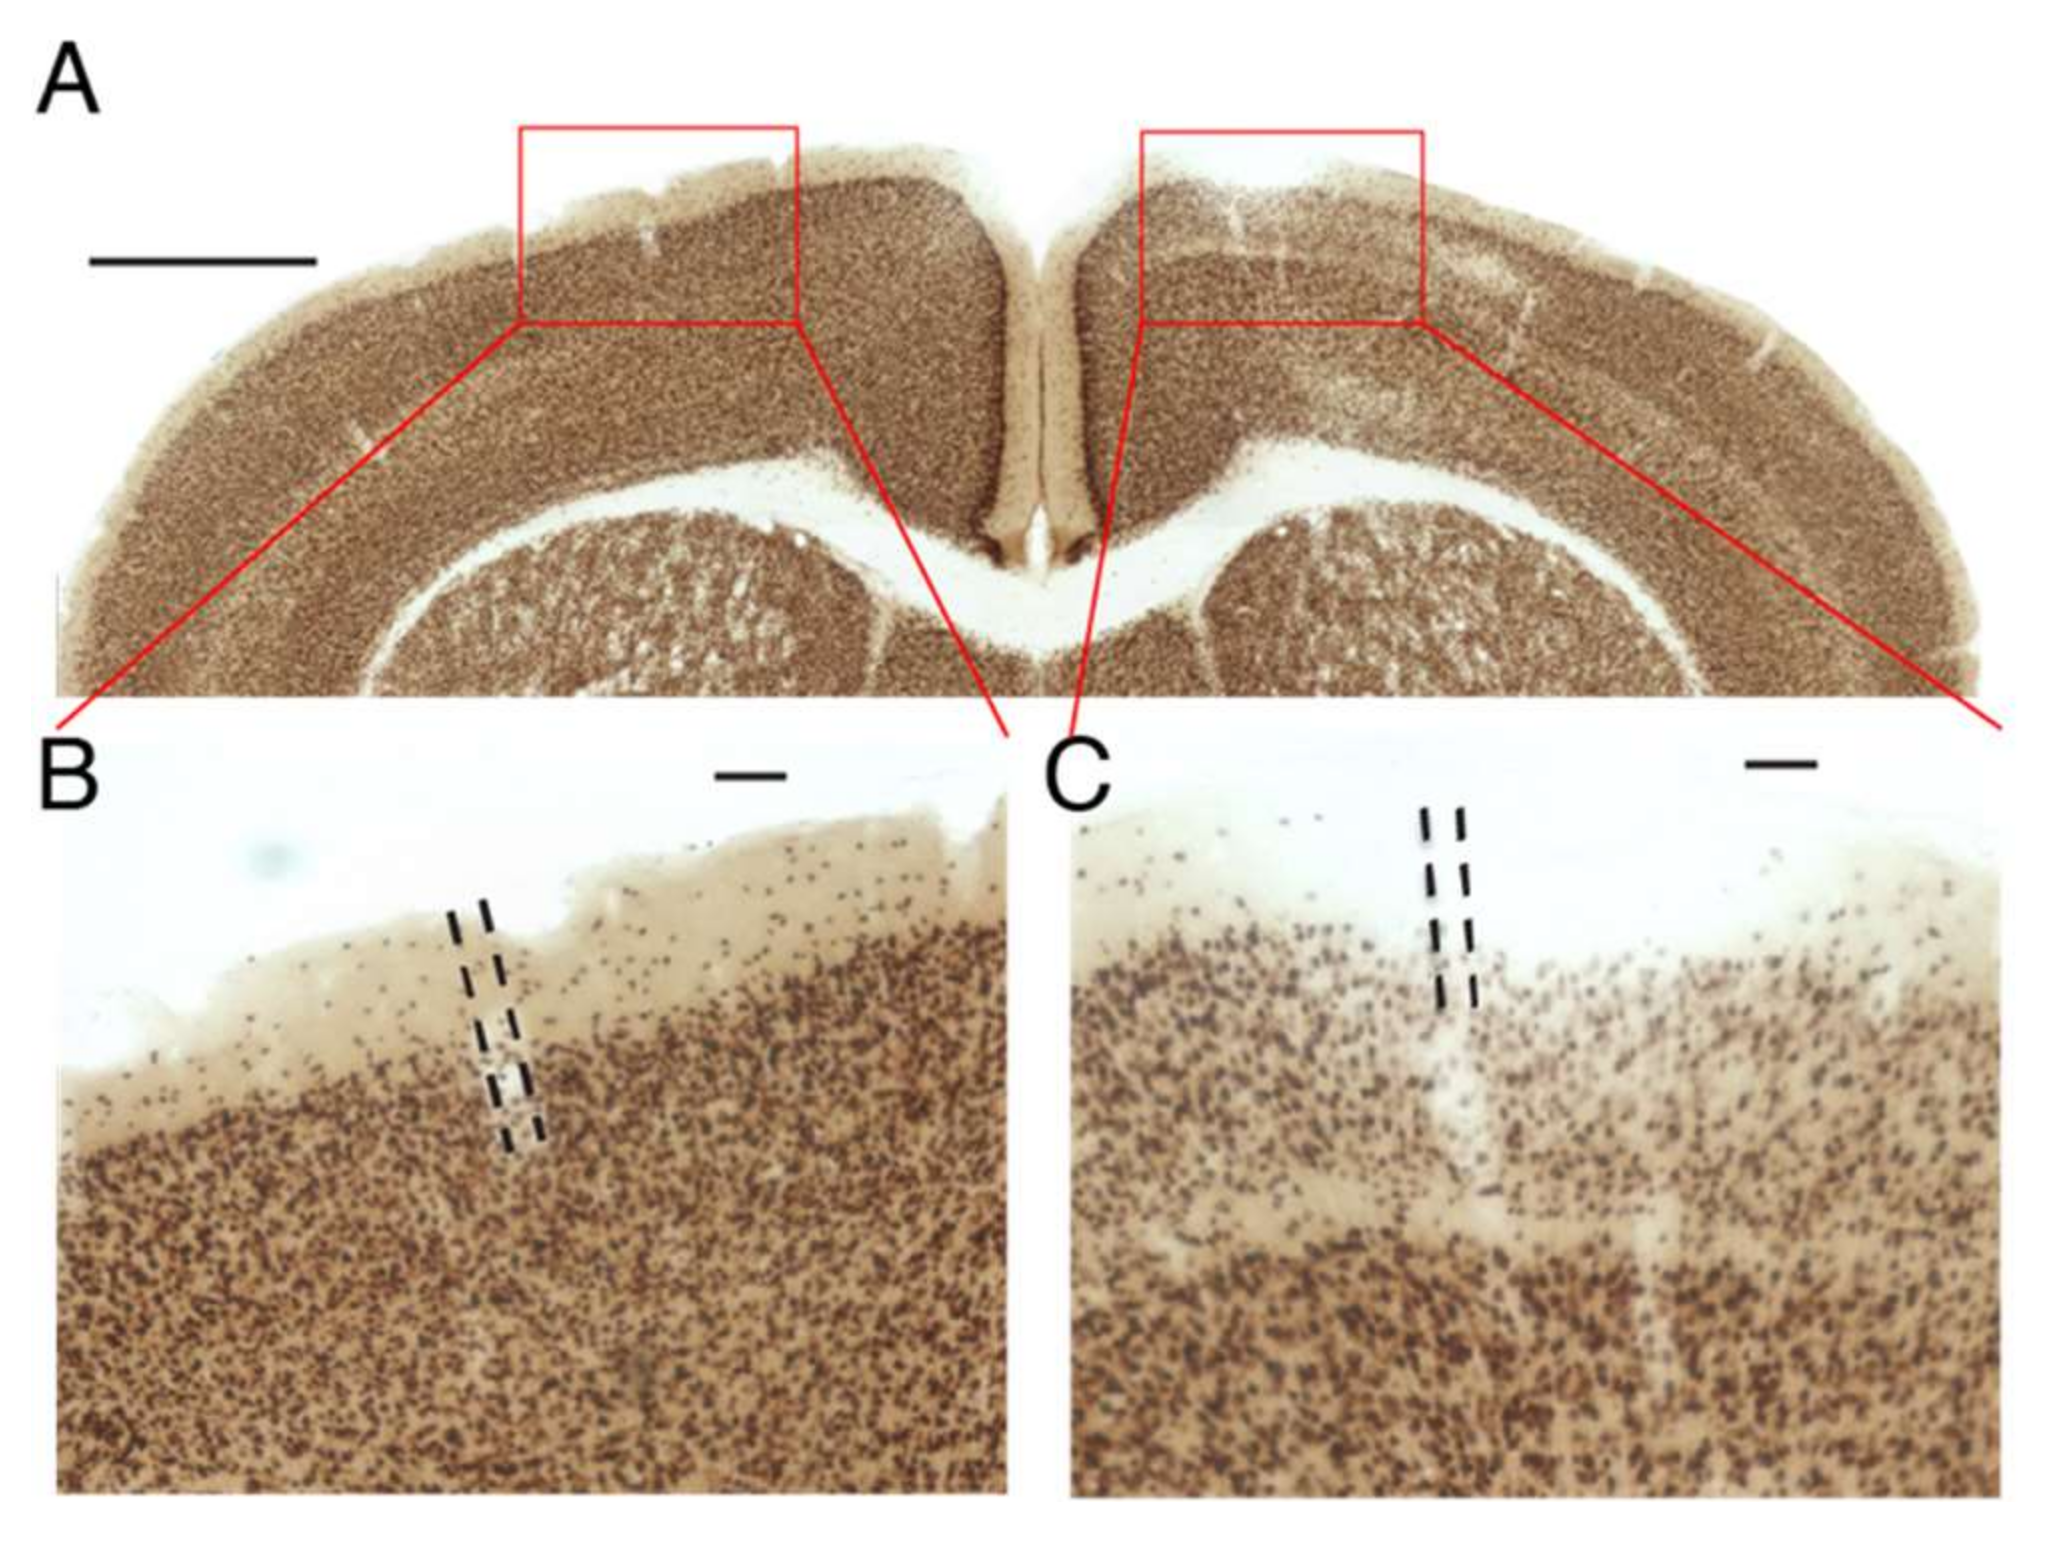

3.4. Unstimulated HGN-Liposome Effectively Sequester Bioactive Compounds In Vivo

One of the potential advantages of HGN-liposome drug delivery is that drugs can be sequestered in the body without activity, until released on demand. That this occurs is suggested by the lack of effect of infusion of muscimol-containing HGN-liposome in the absence of ultrasound stimulation (Figure 5 and Figure 6). To further test the ability of the HGN-liposome used here to sequester bioactive compounds, we loaded HGN-liposome with a neurotoxin, kainic acid (KA), which causes widespread cell death when injected into brain, and injected it into the cerebral cortex. Following one week of survival we examined the effects of the injection on neural tissue. As shown in Figure 7, injection of HGN-liposome containing KA had no effect (Figure 7B), whereas injection of unencapsulated KA solution caused damage to neural tissue, indicated by the pale areas in Figure 7C. Together, these results indicate that the HGN-liposome used here are able to sequester drugs until release is triggered.

Figure 7. Liposomes effectively sequester drugs in vivo. (A) Transverse section of brain stained for cell bodies (NeuN), showing injection sites of KA-containing liposomes (left) and unencapsulated KA solution (right). Red rectangles show location of enlarged images in (B,C). Scale bar, 1 mm. (B,C). Enlargements of sites shown in (A). Dashed lines indicate injection tracks. Scale bar 100 µm.